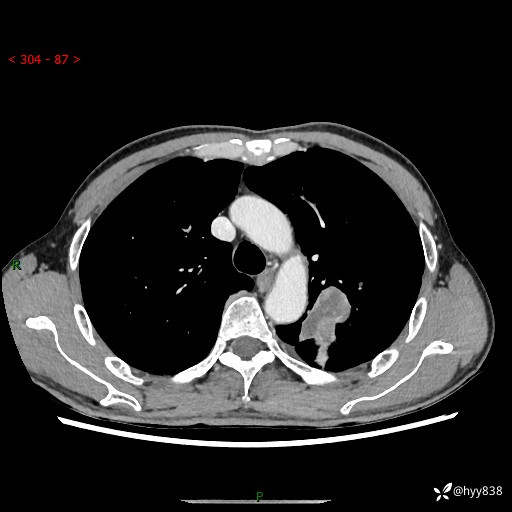

现病史:患者余4月前发现咳嗽咳痰伴痰中带血,无胸闷、胸痛、头晕、恶心、呕吐等不适,2天前因体检发现肺部结节遂于当地市第一人民医院行胸部CT薄层平扫+三维重建示:1.左肺上叶尖后段占位性病变考虑肿瘤性病变伴阻塞性肺炎,右肺上叶后段磨玻璃结节。2.肝内多发囊性灶、左肾结石。现患者为求进一步治疗,于我院门诊就诊,门诊以“肺结节”收入院。 自患病以来,精神、饮食、睡眠尚可,大小便正常,体力体重无明显减轻。

胸部CT增强扫描(外院平扫)